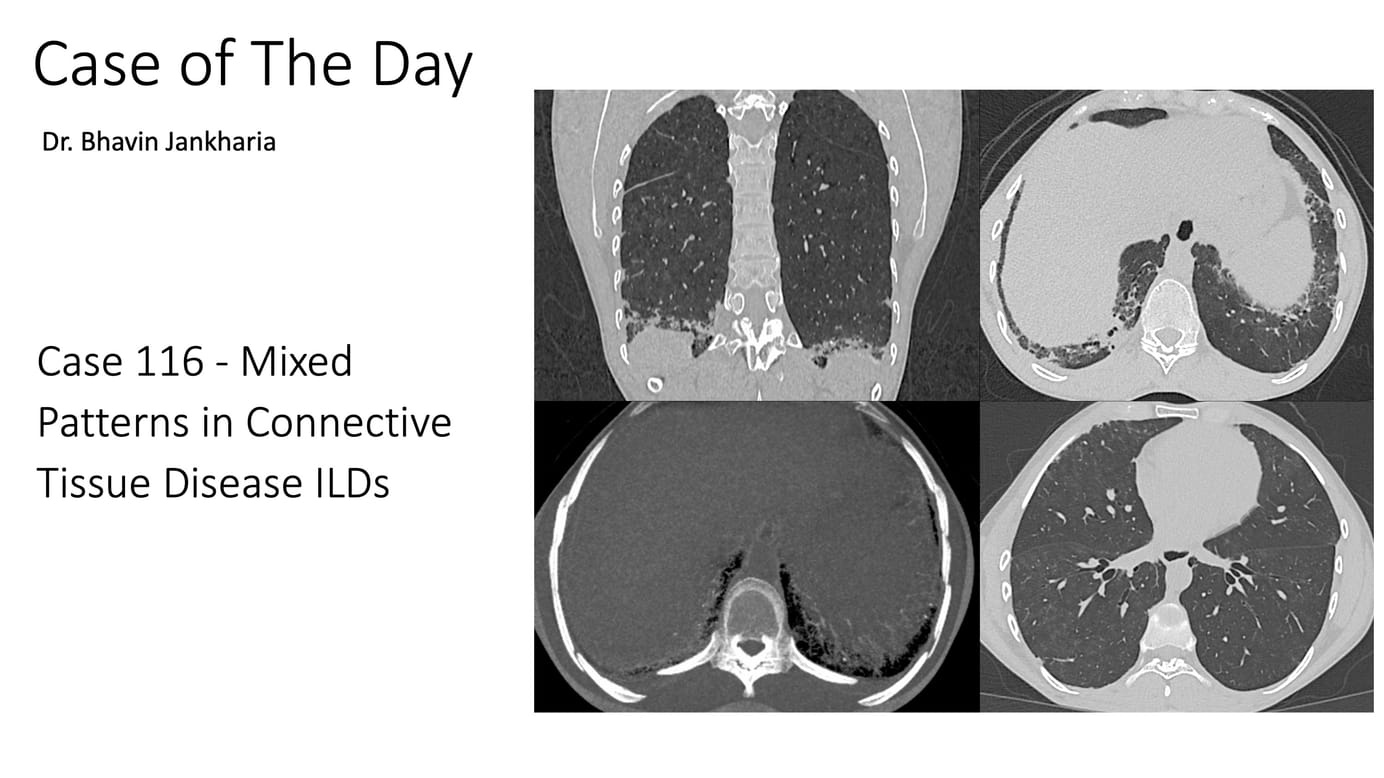

31-yrs old with scleroderma and known scleroderma ILD unchanged for 1 year.

The video describes the case and the 3 different patterns noted - a fibrotic NSIP pattern, a non-fibrotic BIP pattern and DPO, suggesting underlying CiOP - hence a mixed NSIP/BIP/OP pattern.